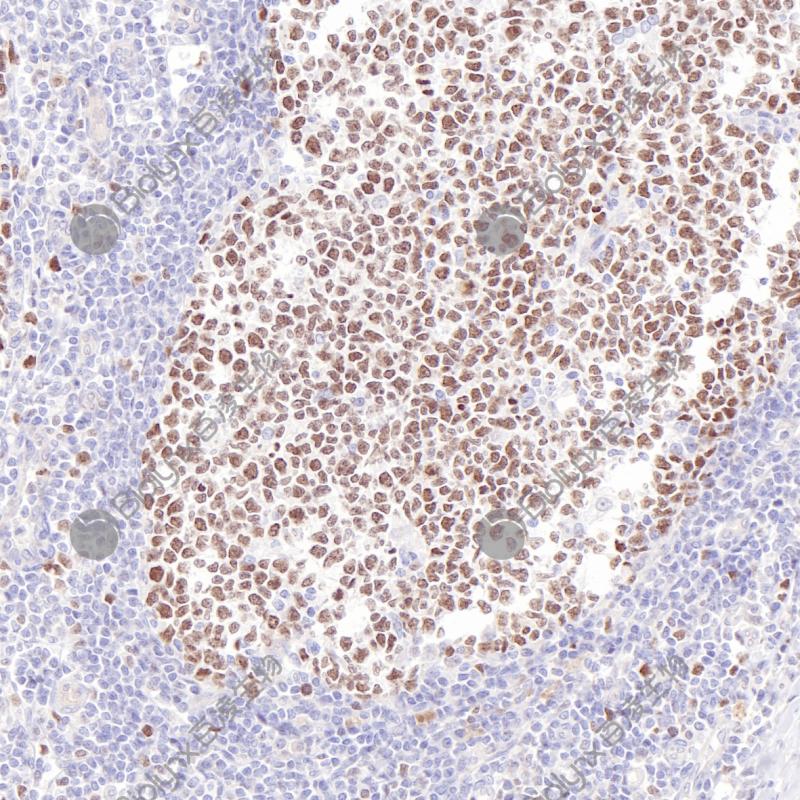

扁桃体EZH2(BP6269)染色

Zeste同源物2增强子(Enhancer of Zeste Homolog 2,EZH2)属于polycomb家族(PcG)。EZH2在许多肿瘤类型中过表达,包括乳腺癌、结肠癌、喉癌、淋巴瘤和睾丸癌。EZH2的高表达与肿瘤的恶性过程、侵袭性和转移能力密切相关。研究表明,EZH2在肿瘤和免疫细胞中的多效性功能,使得 EZH2抑制作为一种极具潜力的方法可以加强现有的免疫治疗,以改善某些癌症患者的预后。

阳性对照

扁桃体

亚细胞定位

细胞核